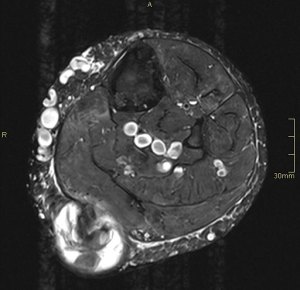

En el corte axial de las imágenes 3 y 4 puedes ver la anatomía radiológica implicada. La relación es perfecta, y completamente explicativa de la situación resulta mediante el tratamiento quirúrgico. En ella la Arteria iliaca derecha para justo por encima de la Vena iliaca Izquierda con la capacidad de poder comprimirla.